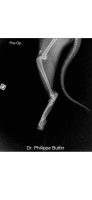

Radiologické snímky